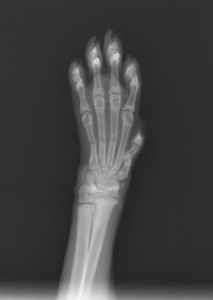

痛がってないのでちょっと様子見・・・時間が経ってもまだ挙げてる・・・腫れてきた・・・折れてるわ・・・ということで、レントゲン・・・

やっぱり・・・折れてるやん!しかも3本も!

獣医学的には内固定しないといけないけど・・・まだ、小さいし・・・外固定で行くか!(急に獣医師目線・・)